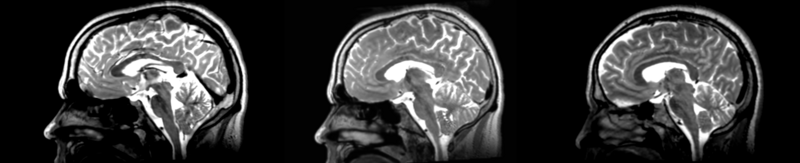

Registration of two different subjects t2 images via the affine selection in the Register Images module.

current20:37, 22 April 2009Thumbnail for version as of 20:37, 22 April 20092,100 × 427 (504 KB)Rauscha (talk | contribs)Registration of two different subjects t2 images via the affine selection in the Register Images module.